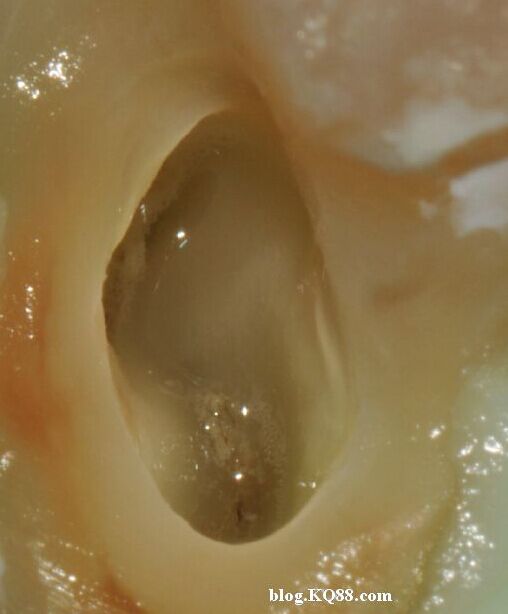

利用兩組照片說明:A因齲拔除的智齒去腐揭髓頂后

暴露牙髓

髓腔內(nèi)放入2%左右的次氯酸鈉,通過氣泡可以看到牙髓已經(jīng)開始溶解。